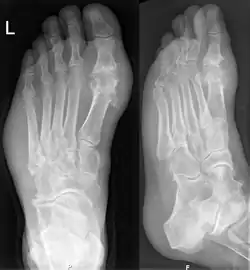

Gout on X-rays of a left foot in the metatarsal-phalangeal joint of the big toe. Note also the soft tissue swelling at the lateral border of the foot.